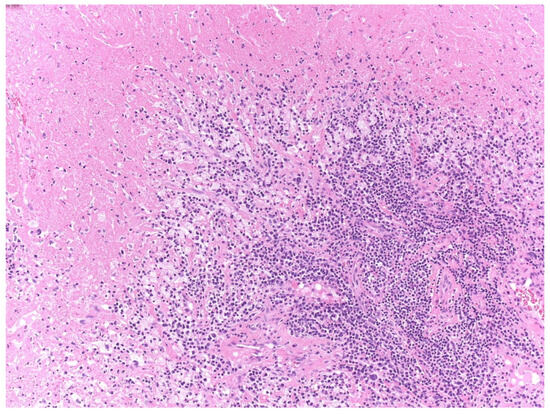

2.3. Pathological Analysis